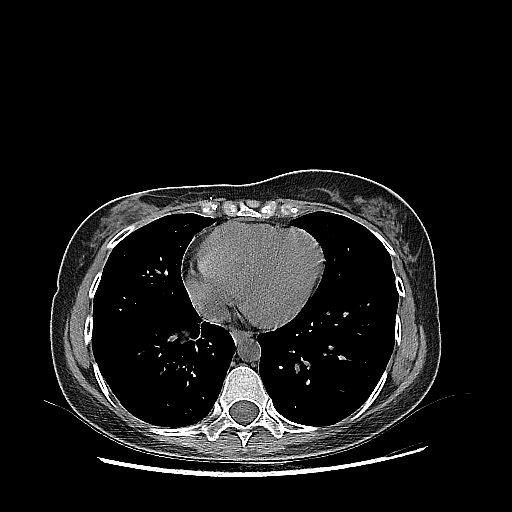

Original NATIVE CT scan (input)

Full window (WL 1023.5, WW 4095 β†’ Low βˆ’1024, High +3071)

Lung window (WL -600, WW 1500 β†’ Low βˆ’1350, High +150)

Mediastinum window (WL 40, WW 400 β†’ Low βˆ’160, High +240)